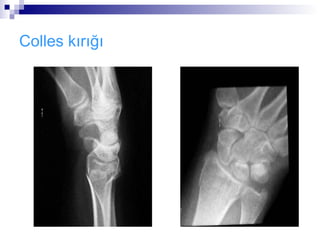

Colles kırığı:

 Distal radius metafiz kırığıdır.

 El üzerine düşme ile meydana gelir

 Radius dorsale deplase olur.

 El bileğinde karakteristik dorsifleksiyon veya çatal

sırtı deformitesi oluşur.

 Medial sinir üzerindeki basınç veya gerilimden

dolayı palmar parestezi vardır.

   AP grafide radius distal metafiz kırığı .

   Lat. grafi dorsal açılanmayı en iyi gösterir.

Colles kırığı